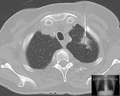

- Biopsie Lunge Computertomographie BC.png 1٬190 × 948؛ 572 كيلوبايت